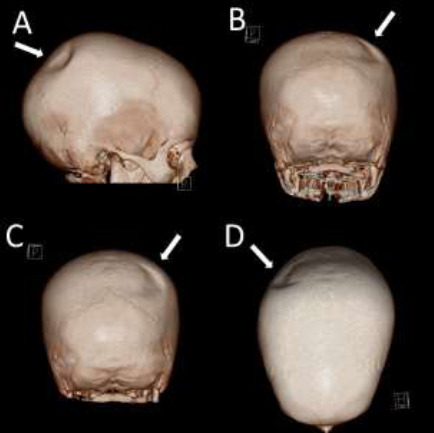

Idiopathic focal unilateral skull thinning is a rare finding. An explanation, such as trauma or disease, can often be found. However, in some cases, no explanation is forthcoming, and thus, we must look further into their history for a possible cause. The case of a nine-year-old boy with a crescent-shaped unilateral parietal bone thinning and a history of ventouse-assisted birth is presented. The lesion matches a ventouse's typical location, shape, and size. Thus, with the support of one other reported similar case, we hypothesise this may be the origin. We present the case of a crescent-shaped lesion matching the imprint of a ventouse in a child with a concordant history. This finding is put in the context of similar reports in the literature, and we believe that this report provides further evidence of this obscure phenomenon.